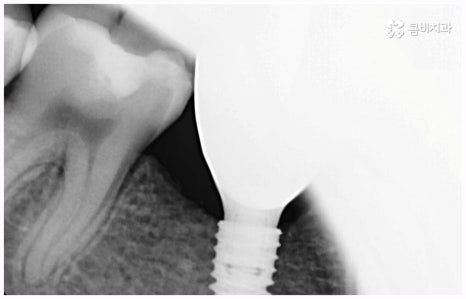

이러한 치아 상실에 대해 예전에는 틀니와 브릿지 시술을 많이 받았지만 요즘 대세는 임플란트 식립이라고 할 수 있어요. 틀니처럼 탈락의 위험이 잦거나 음식을 먹을 때 제약이 크게 따르지 않으며 브릿지처럼 양 옆 치아를 제거하지 않아도 되는 임플란트는 치아가 빠진 잇몸에 직접 티타늄 인공 치근(픽스처)을 심은 다음 지대주(연결 부위)를 이어주고 크라운(치아 머리 보철물)을 씌워 수복을 하는 것이기 때문에 저작 능력의 회복이 탁월하고 겉에서 봤을 때 거의 자신의 치아와 다름없이 자연스럽게 보인다는 장점으로 인해 많은 분들이 선호하시는 거예요.

비용이나 시간적인 부담이 만만치 않기 때문에 임플란트를 보다 오랜 기간 동안 건강하게 사용하려면 어떻게 해야 하는지 궁금해 하시는 분들이 많이 있으실 거예요. 임플란트 식립 성공률 및 지속률에 가장 크게 영향을 주는 것은 환자분들의 잇몸뼈 건강 상태 및 술자의 숙련도라고 할 수 있는데요. 예를 들어 구강 질환을 원인으로 한 병증이 심각하거나 치아를 상실한지 오랜 시간이 지나 잇몸뼈의 흡수가 많이 일어났기 때문에 높이와 밀도 등이 식립을 진행하기에 충분하지 않다면 뼈이식을 선행하여 기반부터 튼튼하게 보충해 줄 필요가 있어요. 또한 노화로 인해 상악동이 내려왔다면 상악동 거상술을 통해 공간을 확보해 주어야 하는데 이렇게 고난도 수술의 경우 다양한 임상 경험을 통해 풍부한 노하우와 뛰어난 기술력을 가지고 있는 의료진과 함께 하는 것이 무엇보다 중요하다고 할 수 있습니다.

임플란트는 관리를 철저하게 해 준다면 거의 반영구적으로 쓸 수 있다고 알려져 있을 만큼 잘 유지 관리하는 것이 굉장히 중요한데, 그 첫 단계가 정확한 위치와 각도로 식립하는 과정이라고 할 수 있어요. 임플란트가 잘못된 위치에 식립되거나 너무 깊게 또는 얕게 식립되면 교합이 잘 맞지 않고 저작 활동을 할 때 무리가 가 잇몸병을 유발함으로써 임플란트의 수명을 줄일 수 있기 때문인데, 이때 임플란트 제작시 커스텀 지대주를 사용하면 환자분들의 구강 구조에 정확하게 맞는 각도로 보철물을 식립할 수 있어서 더욱 편안한 사용을 할 수 있을 거예요. 식립 후 너무 많이 딱딱하거나 끈끈한 음식은 조심하시는 편이 좋으며, 이후 꾸준하고 지속적인 검진 및 스케일링 치료를 통해 위생을 청결하게 해 주면 임플란트 수명을 연장하는데 도움이 될 수 있습니다.